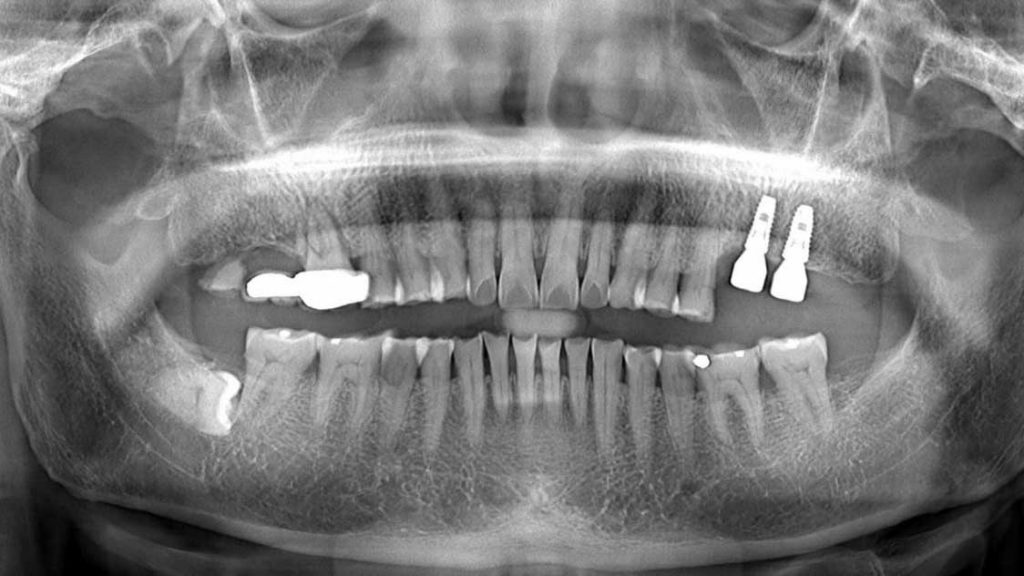

Hiện nay, kỹ thuật cấy ghép implant là một kỹ thuật giúp phục hồi chiếc răng bị mất một cách hoàn hảo, với kỹ thuật tiên tiến hiện đại bậc nhất hiện nay. Được nhiều người dân Việt Nam biết đến và đã, đang, sẽ sử dụng phương pháp này trong trường hợp mất răng. Nguyên tắc của phương pháp này là cấy chân răng giả vào xương hàm của bệnh nhân bị mất răng. Rồi sau đó một thời gian khi chân răng dính vào xương hàm thì nha sĩ sẽ chụp phần răng sứ lên trên vừa khít với khoảng trống răng mất, vừa đảm bảo khả năng ăn nhai và hiệu quả thẩm mỹ.

Các chân răng implant được cố định một cách chắc chắn trong xương hàm nhờ quá trình trụ được tích hợp với xương. Nhờ vậy mà răng sau khi trồng tạo được lực nhai khá tốt sau khi điều trị. Kỹ thuật cấy ghép implant giúp khắc phục hiệu quả tối đa tình trạng bị mất một răng hay nhiều răng hay mất răng toàn bộ. Với các bệnh nhân bị mất nhiều răng thì lựa chọn phương pháp implant chính là tốt nhất, hiệu quả nhất. Bởi nó giúp phục hồi phần chân răng đã mất, người bệnh không cần đeo hàm giả, răng chắc khỏe hơn cả răng thật, tự do ăn nhai thoái, răng đều đẹp tự tin mang lại sự cân đối hài hòa cho gương mặt.

- Chụp CT và khảo sát kết quả thông qua phần mềm thông minh

- Tiến hành cấy ghép một trụ implant titanium vào xương hàm, thông thường gồm 4 trụ (2 trụ phí trước được cấy ghép thẳng và 2 trụ phía sau được cấy ghép nghiêng).